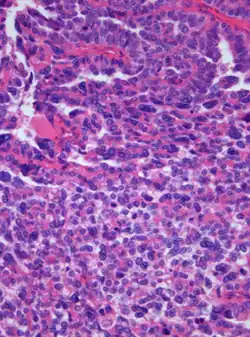

Photomicrograph of hematoxylin-eosin stained section of a choroid plexus carcinoma (grade III WHO) at 400x magnification

A choroid plexus carcinoma (WHO grade III) is a type of choroid plexus tumor[1] that affects the choroid plexus of the brain. It is considered the worst of the three grades of chord plexus tumors, having a much poorer prognosis than choroid atypical plexus papilloma (WHO grade II) and choroid plexus papilloma (WHO grade I).[2] The disease creates lesions in the brain and increases cerebrospinal fluid volume, resulting in hydrocephalus.[3]